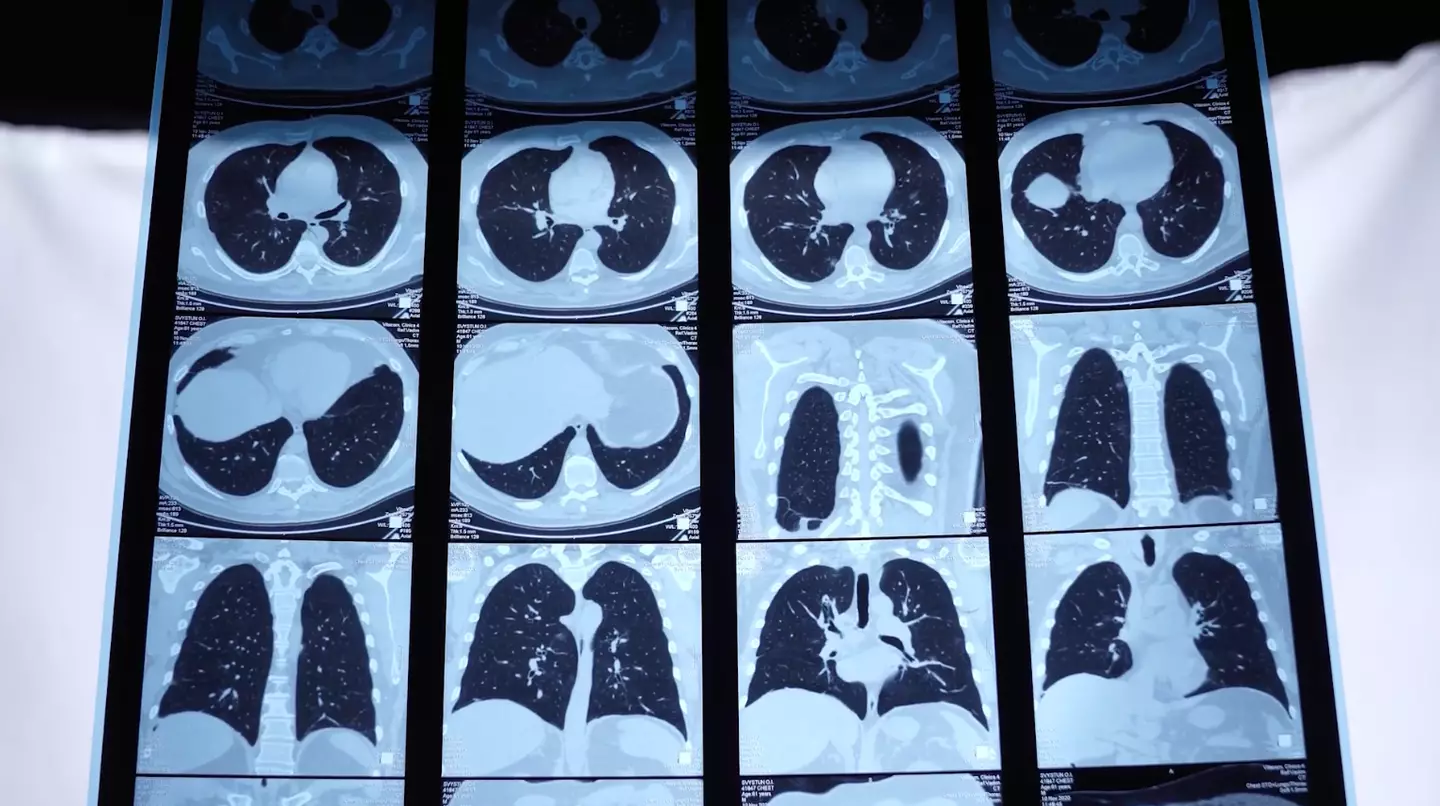

Reported by The i paper, she said: “In my clinic, the average age of patients is 31; the youngest is 23, who I’ve just referred for a lung transplant…these are young men, and they have only had a few years of exposure to silica, and even if they were having the current health surveillance program and the chest X-ray after, say, 10 years, they are not going to be picked up.”

The number of confirmed cases has risen by around 460 per cent in just a year, from eight to 45, according to Dr Feary, who described watching the 'disaster of engineered stone silicosis unfold' around the world. Australia has already banned quartz after hundreds of workers were diagnosed there.